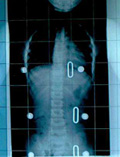

平成19年2月13日

60度で来院

レントゲン平成19年2月13日